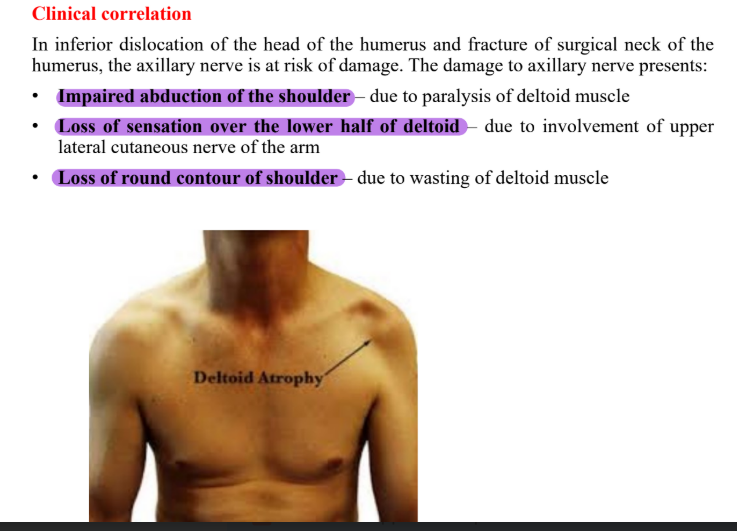

Clinical correlation of shoulder